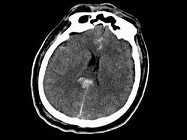

- 单项选择题男,25岁, 头颅外伤,昏迷, 意识丧失,结合CT图像, 最可能的诊断是 ( )

A、结节性硬化病

B、脑剪切伤

C、脑囊虫病

D、脑实质钙化灶

E、脑转移瘤